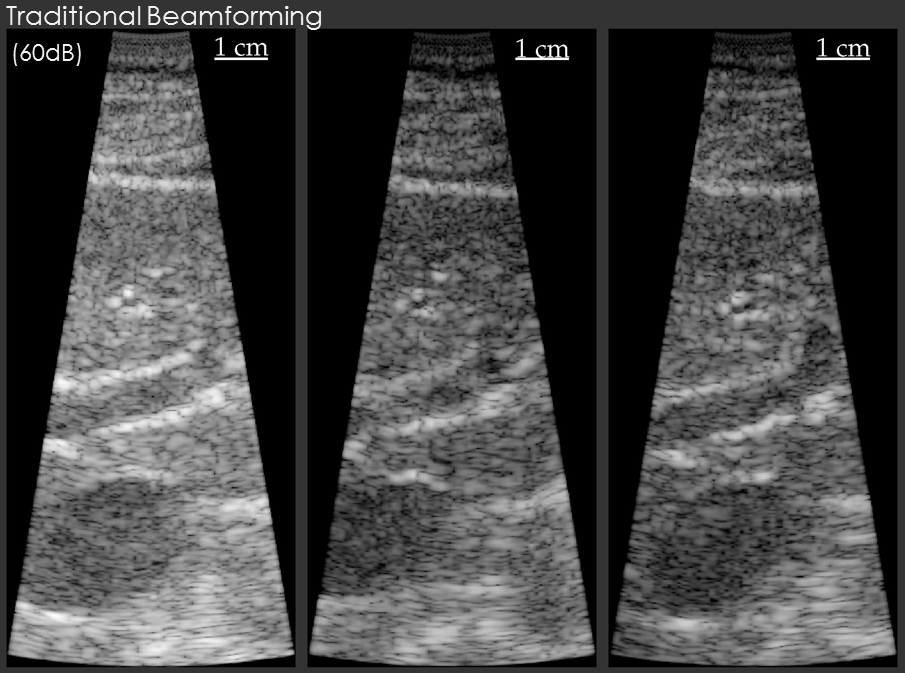

Example results are shown below for our model-based beamformer applied to in vivo human data.

In the first example, the data beamformed using traditional methods has a “hazy” appearance that is common in in vivo imaging. The image beamformed using the model-based beamformer appear significantly sharper. The result is compelling, but a common criticism is that the same result could be obtained by changing the compression on the ultrasound scanner. To address this criticism another set of example data is shown. The second set of example data shows 3 images of the same structure in the same patient. When the data from the patient is beamformed using traditional methods the bile duct is not visible. When the data is beamformed using a model-based approach the bile duct is present in each case. The notable aspect of this example is that changing the system compression would not enable the visualization of the bile duct.